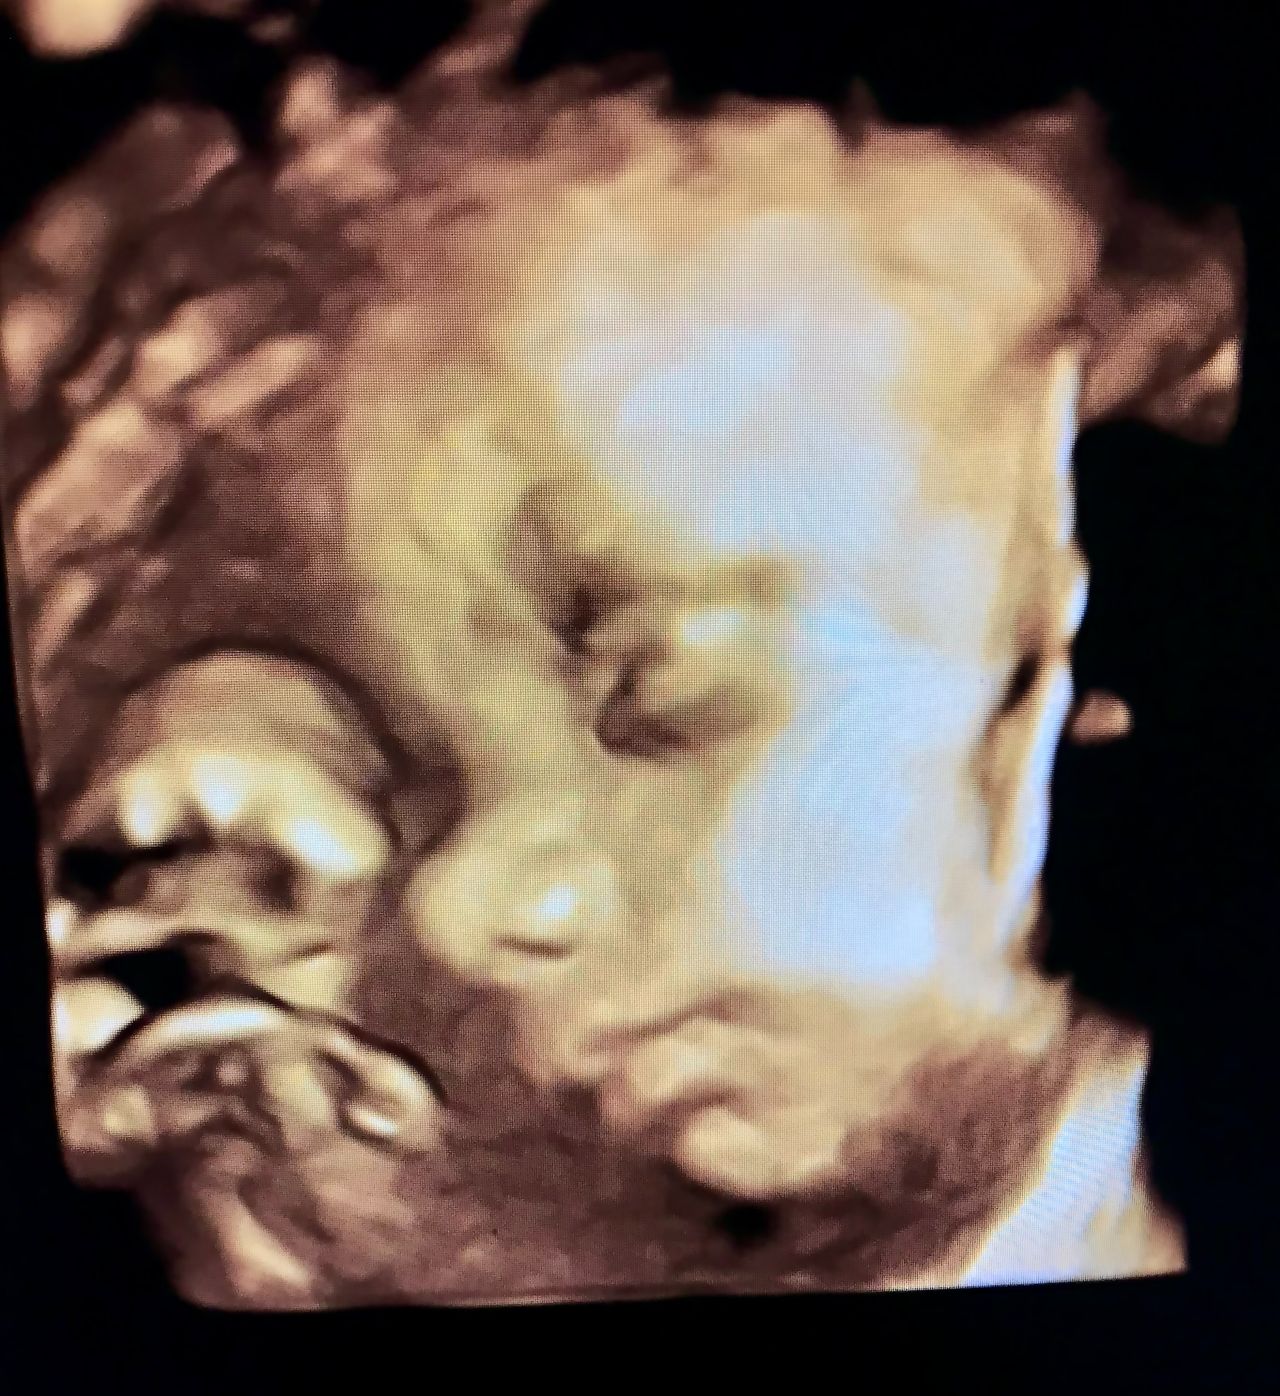

Dzięki szerokiemu doświadczeniu klinicznemu i możliwości poznania najlepszych praktyk zagranicznych zajmuję się pełnym zakresem opieki ginekologicznej. Przeprowadzam wizyty kontrolne, przygotowuję do ciąży, diagnozuję i leczę niepłodność, dobieram antykoncepcję, leczę infekcje intymne. Prowadzę zarówno ciąże fizjologiczne, jak i powikłane, w tym m.in. cukrzycą ciążową, nadciśnieniem czy ryzykiem porodu przedwczesnego. Wykonuję USG ginekologiczne oraz prenatalne - również 3D i 4D. Przeprowadzam cięcia cesarskie oraz małoinwazyjne zabiegi ginekologiczne.

- USG ciąży - w tym badania referencyjne I, II, III trymestr, 3D/4D - aparat GE Voluson E10 i E8